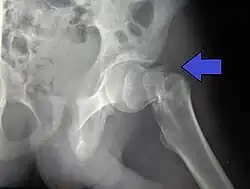

X-rays of the affected hip usually make the diagnosis obvious; AP (anteroposterior) and lateral views should be obtained.

For low-grade fractures (Garden types 1 and 2), standard treatment is fixation of the fracture in situ with screws or a sliding screw/plate device. This treatment can also be offered for displaced fractures after the fracture has been reduced.

Fractures managed by closed reduction can possibly be treated by percutaneously inserted screws.[38]

In elderly patients with displaced or intracapsular fractures surgeons may decide to perform a hemiarthroplasty, replacing the broken part of the bone with a metal implant.[39] However, in elderly people who are medically well and still active, a total hip replacement may be indicated. Independently mobile older adults with hip fractures may benefit from a total hip replacement instead of hemiarthroplasty.[40]